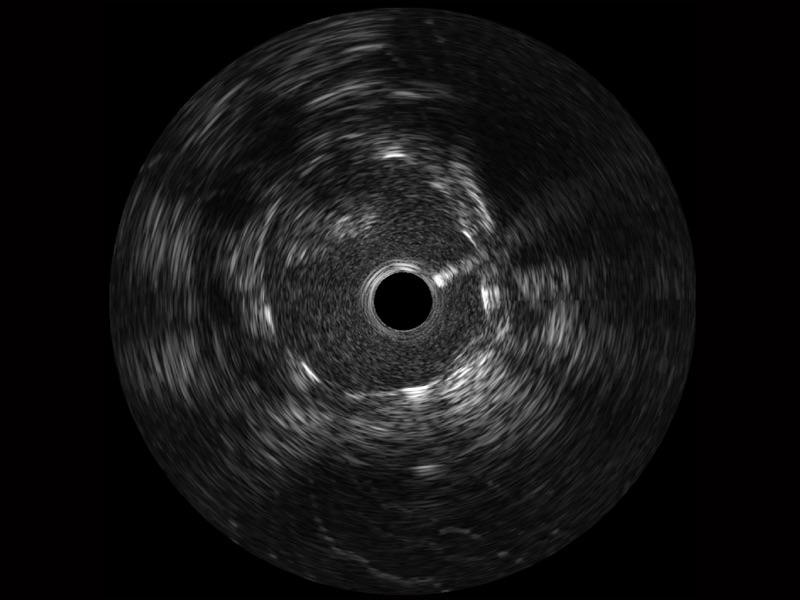

• 环球UG官网宽频IVUS图像

对比传统IVUS导管成像,环球UG官网宽频IVUS图像的近场支架梁显影更细腻,远场中膜外血管仍清晰可辨,兼顾远中近,兼顾分辨力与穿透深度